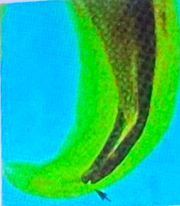

to file away from the inner curve of a root to reduce the risk of strip perforation

technique in multirooted teeth: filing is concentrated on the bulky or safety zone using a push-and-pull motion, away from the danger zone.

danger zone: always the inner surface of the tooth.

safety zone reference:

if distal root, safety zone = mesial.

if mesial root, safety zone = distal.

strip perforation